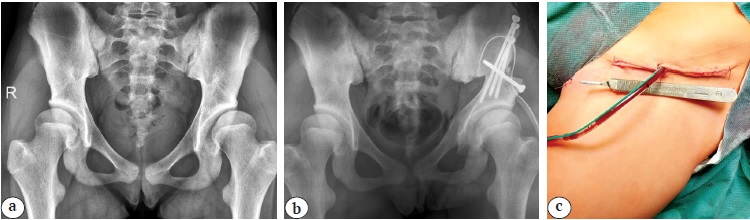

Переднебоковой доступ. Положение пациента на операционном столе — лежа на контралатеральном пораженному суставу боку. Выполняется углообразный разрез кожи и подкожно-жировой клетчатки от передне-верхней ости подвздошной кости до уровня границы верхней третей диафиза бедра длиной 15–20 см. Рассечение tensor fascia lata повторяет разрез кожи с дополнительным поперечным сечением кзади на уровне большого вертела с целью проведения манипуляций на седалищной кости. После препаровки промежутка между m. gluteus medius и m. tensor facia lata и выделения крыла подвздошной кости осуществляется рассечение хрящевого апофиза гребня подвздошной кости с последующим поднадкостничным выделением тела подвздошной кости, в которую проводится проволочная пила. Следующим этапом выполняются поднадкостничное выделение и остеотомия лонной кости медиальнее Y-образного хряща или гребневидного бугорка максимально близко к вертлужной впадине. После выделения на протяжении n. ischiadicus выполняются поднадкостничное выделение и периацетабулярная остеотомия седалищной кости краниальнее места прикрепления lig. sacrotuberosus. После этого проводится остеотомия тела подвздошной кости с последующей реориентацией либерализованной вертлужной впадины (рис. 1).

Рис. 1. Выполнение тройной остеотомии таза из переднебокового хирургического доступа: a — рентгенограмма пациента 12 лет с дисплазией тазобедренных суставов I степени по Crowe до операции; b — рентгенограмма после восстановления корректных соотношений между тазовым и бедренным компонентами тазобедренного сустава методом реориентирующей тройной остеотомии таза справа; c — фото хирургического доступа после ушивания